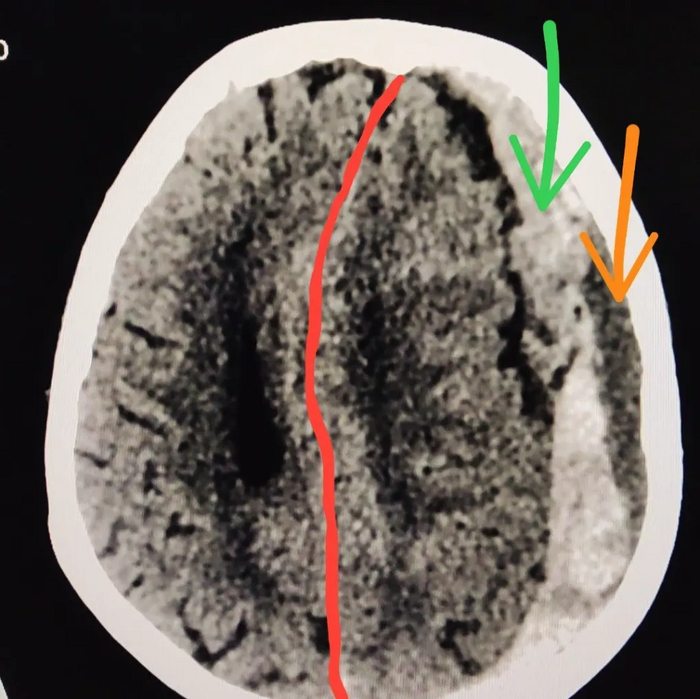

Женщина 85 лет. Вызвала скорую помощь с жалобами на повышение артериального давления до 200/120 мм.рт.ст. и головную боль. По приезде сотрудников скорой помощи у пациентки возникла неукротимая рвота, а затем и угнетение сознания до комы. В течение 3 минут была доставлена в ближайшую больницу.

При осмотре: сознание -умеренная кома. Снижен мышечный тонус в правых конечностях, сухожильные рефлексы справа не вызываются.

На КТ головного мозга субдуральная гематома слева (на картинке она справа, обведена красным цветом)

Со смещением срединных структур мозга ( обозначено красной линией)

Также можно заметить что в гематоме есть кровь разной плотности. Под зелёной стрелкой свежее кровоизлияние, а под оранжевой старое кровоизлияние, которое произошло, возможно, днями или неделями ранее.

Пациента экстренно направлена в нейрохирургическое отделение для определения дальнейшей тактики лечения - удаления гематомы хирургическим путем.

Дальнейшая судьба пациентки пока не известна